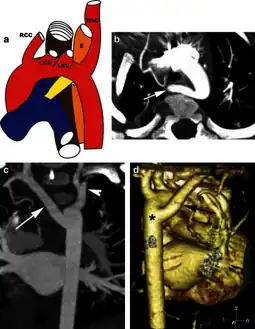

Aberrant subclavian artery on MR angiography.

Aberrant subclavian artery is a rare anatomical variant of the origin of the right or left subclavian artery. It is the most common congenital vascular anomaly of the aortic arch,[1] occurring in approximately 1% of individuals.[1][2][3]

This condition is usually asymptomatic.[1] The aberrant artery usually arises just distal to the left subclavian artery and crosses in the posterior part of the mediastinum on its way to the right upper extremity.[2] In 80% of individuals it crosses behind the esophagus.[2] Such course of this aberrant vessel may cause a vascular ring around the trachea and esophagus. Dysphagia due to an aberrant right subclavian artery is termed dysphagia lusoria, although this is a rare complication.[2][3] In addition to dysphagia, aberrant right subclavian artery may cause stridor, dyspnoea, chest pain, or fever.[1] An aberrant right subclavian artery may compress the recurrent laryngeal nerve causing a palsy of that nerve, which is termed Ortner's syndrome.[4]

The aberrant right subclavian artery frequently arises from a dilated segment of the proximal descending aorta, the so-called Diverticulum of Kommerell (which was named for the German radiologist Burkhard Friedrich Kommerell (1901–1990), who discovered it in 1936).[5][6] It is alternatively known as a lusorian artery.[1][3]